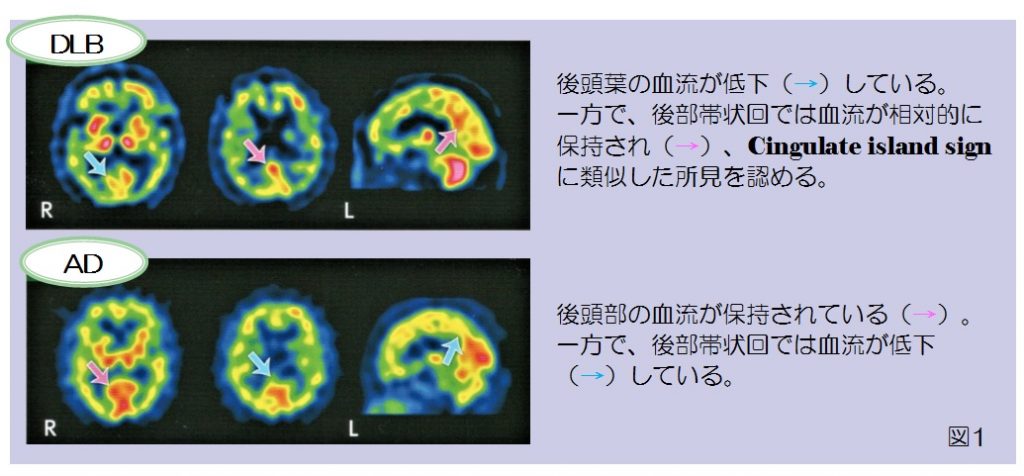

脳のSPECT 機能画像のよみ方・使い方 脳血流SPECT画像 認知症原因疾患ごとの血流分布と読影の注意点1の詳細情報

脳血流SPECT画像 認知症原因疾患ごとの血流分布と読影の注意点1。脳血流SPECT統計解析ソフトウェア (e-ZIS) が新しくなりました。SPECT検査 横浜市。脳のSPECTに関する機能画像の解説と使用法を詳述した専門書。RI検査(SPECT:スペクト検査)|放射線科|診療科のご案内。- タイトル: 脳のSPECT 機能画像のよみ方・使い方- ISBN: 9784524201716- 価格: 15000円ご覧いただきありがとうございます。ぜりー様、専用。